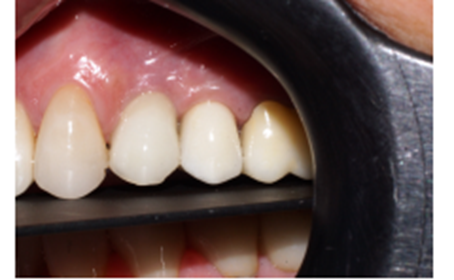

Diante das circunstâncias, foi eleito um pilar Ideale reto de 3.3 X 4.0 X 1.5 mm de transmucoso, que foi instalado a 20 Ncm. O escaneamento desse pilar foi realizado para a confecção de um provisório fresado em PMMA. Após 15 minutos da instalação e do escaneamento do pilar, o provisório fresado foi instalado sobre o pilar Ideale e aparafusado com o parafuso Torx a 10 Ncm. Foi então realizada uma radiografia após a instalação e a paciente foi marcada para retornos de 7 e 15 dias, sendo que após os retornos, a paciente realizou sua viagem (Figuras 11, 12, 13 e 14).

Após cinco meses, a paciente retornou da viagem do exterior, o provisório foi removido e um novo escaneamento foi realizado, copiando assim, o perfil de emergência alcançado através do provisório. As informações foram enviadas para o laboratório e o provisório foi reinstalado (Figuras 15, 16, 17, 18, 19 e 20).

No laboratório foi realizado um novo projeto e o elemento 25 foi fresado em zircônia multilayer na cor A2. Em seguida, maquiado para deixá-lo semelhante aos dentes adjacentes.

Na consulta seguinte a coroa final foi instalada e aparafusada com o parafuso Torx, e o orifício foi restaurado com resina fotopolimerizável. Foi realizada uma radiografia final e a paciente foi remarcada para retornar em seis meses para consulta de controle.